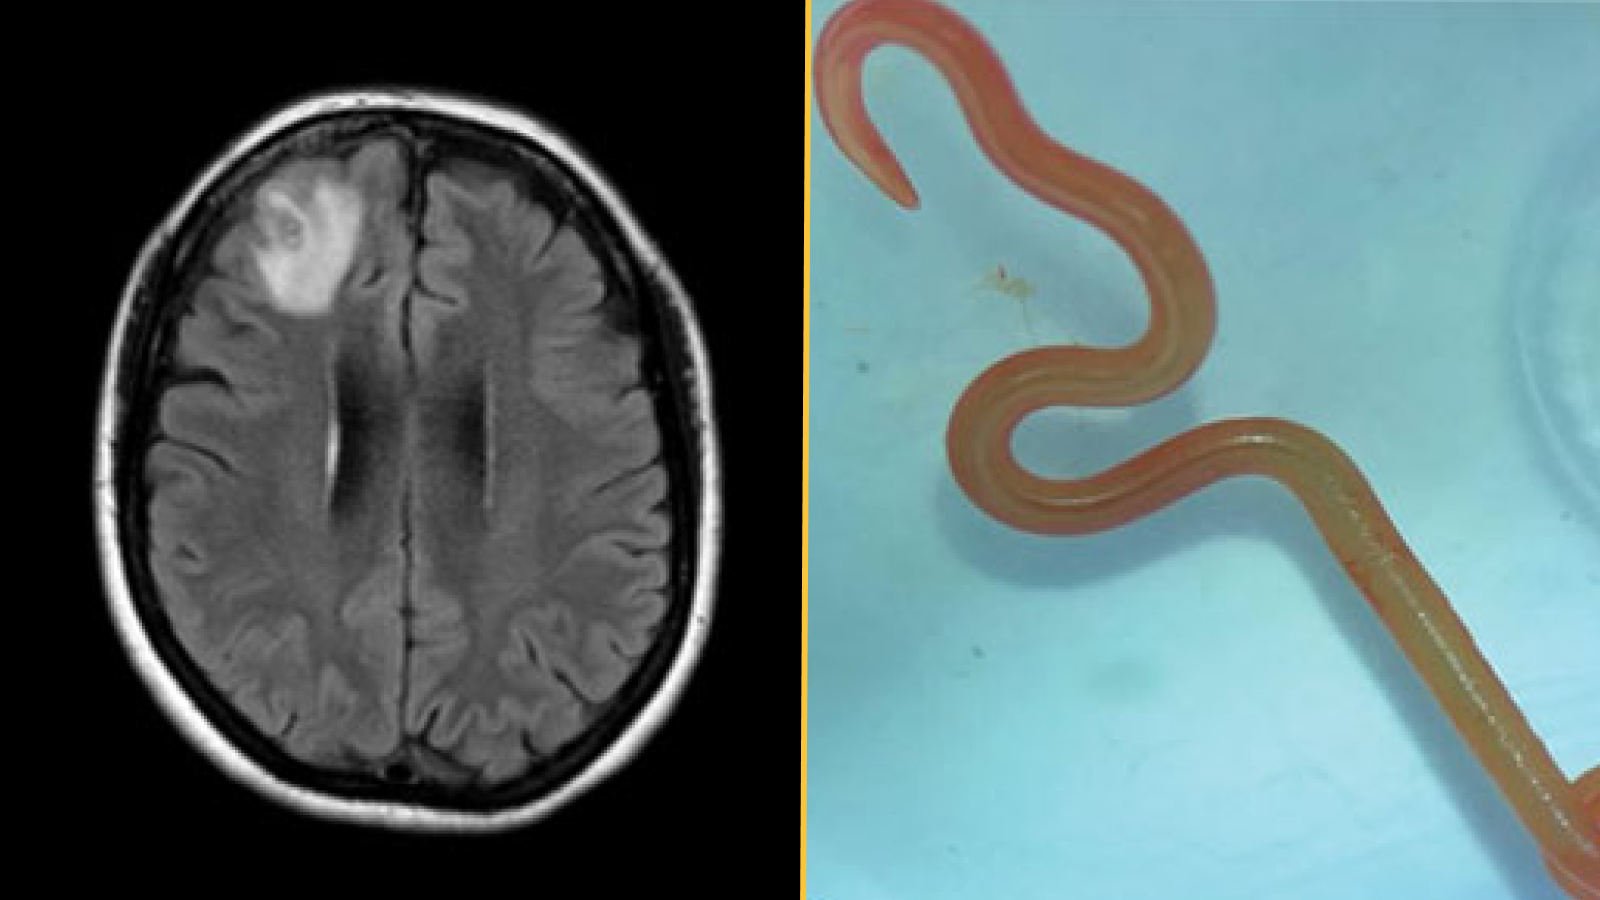

The worm was bright red and measured about 3 inches (80 millimeters) long and 0.04 inches (1 millimeter) thick.

What makes the case unique: The doctors identified the helminth as a third-stage larva of Ophidascaris robertsi, a type of parasitic nematode native to Australia. The adult worms reproduce inside carpet pythons (Morelia spilota), but the nematode can infect other animals during the larval stages of its life cycle.

Carpet pythons were common near the woman’s lakeside home, and although she did not recall having any direct contact with snakes, she often foraged wild greens for cooking. She likely became infected after touching or eating plants contaminated by O. robertsi eggs, the case report authors suggested. After the eggs hatched, the larvae migrated to her organs.